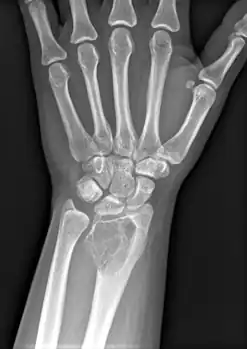

On X-ray, giant-cell tumors (GCTs) are lytic/lucent lesions that have an epiphyseal location and grow to the articular surface of the involved bone.[11] Radiologically the tumors may show characteristic 'soap bubble' appearance.[12] They are distinguishable from other bony tumors in that GCTs usually have a nonsclerotic and sharply defined border. About 5% of giant-cell tumors metastasize, usually to a lung, which may be benign metastasis,[13] when the diagnosis of giant-cell tumor is suspected, a chest X-ray or computed tomography may be needed. MRI can be used to assess intramedullary and soft tissue extension.

Front view X-ray. A well-defined expansile lesion in radius near wrist

Side view of same wrist

Front view X-ray one-year later it has grown